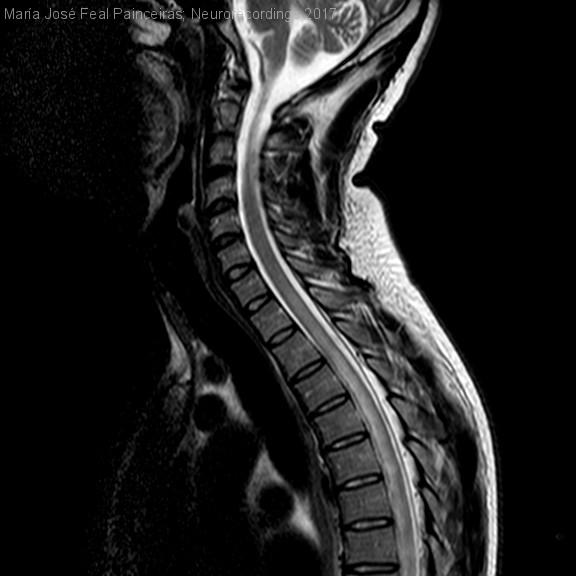

Mielitis transversa como debut de una enfermedad de Behçet

Hombre | 32 años

Diagnóstico final: NeuroBehçet

Paciente de 32 años, natural de Camerún. Ingresa por cuadro agudo de dolor lumbar intenso asociado a debilidad progresiva en miembros  inferiores, llegando a presentar paraparesia (BM 2-3/5), hipoestesia con nivel sensitivo D8 y retención...